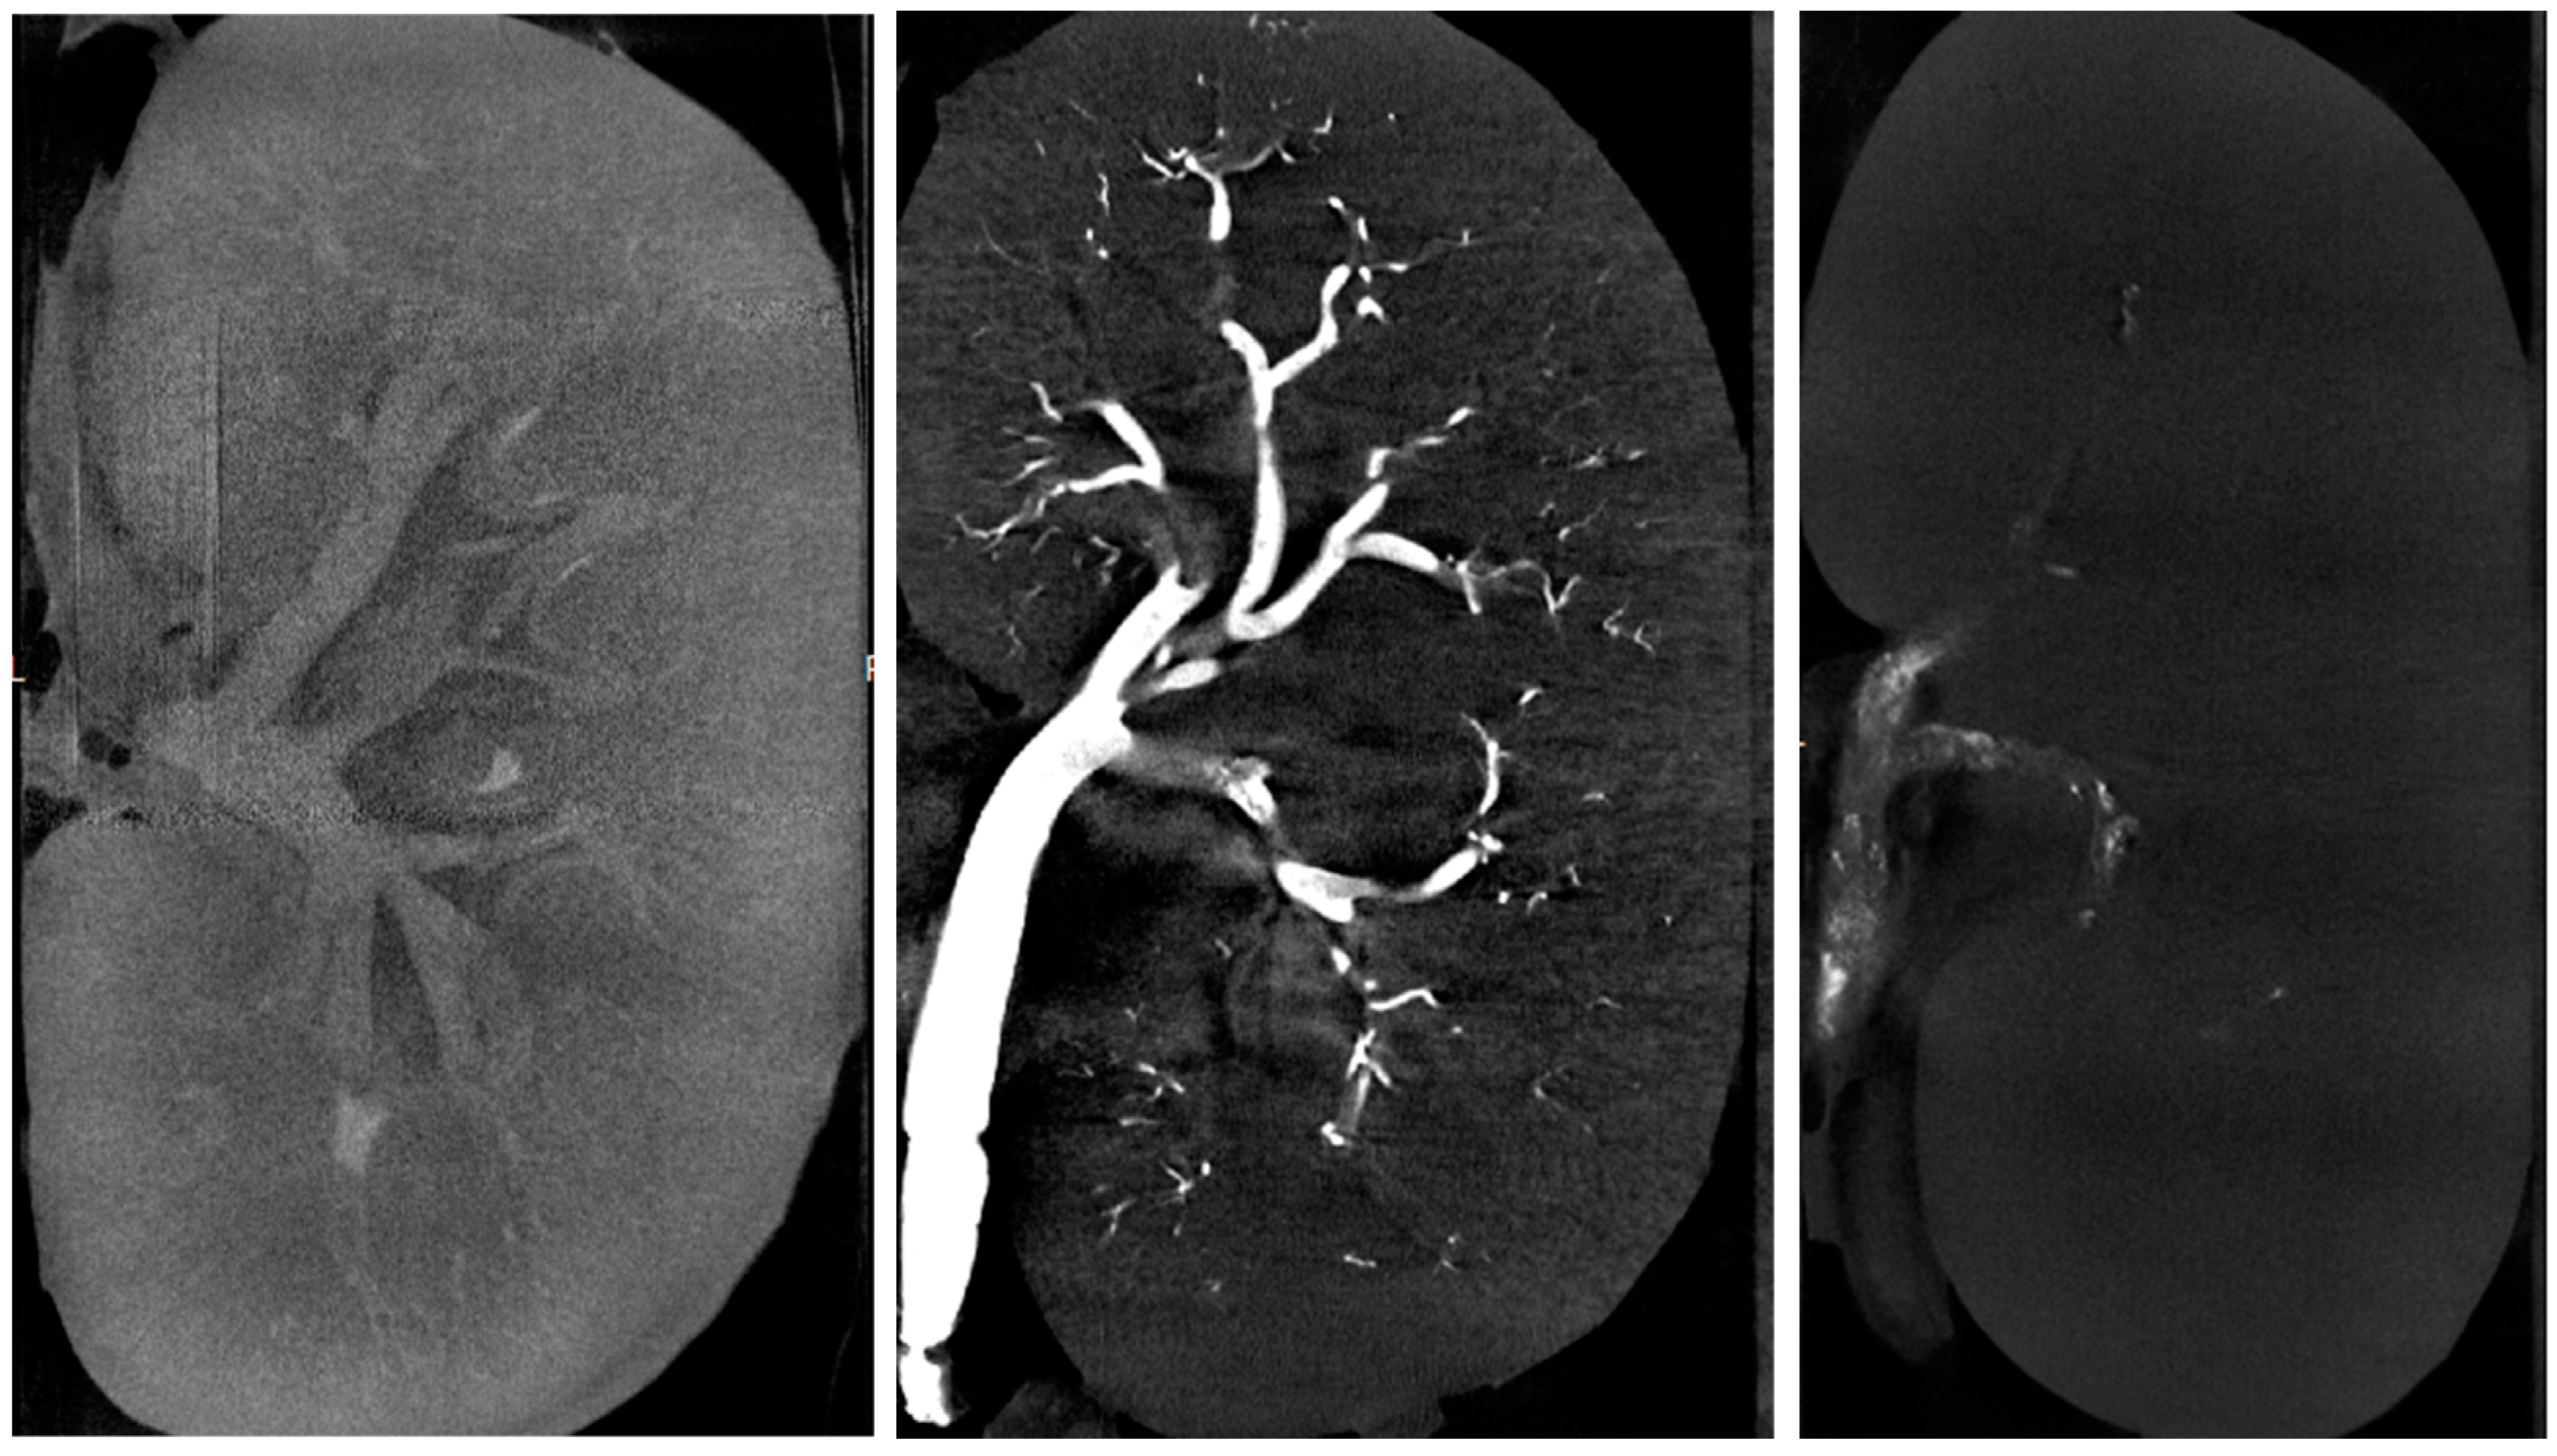

2.2. Micro-Computed Tomography

2.2.1. Acquisition and Reconstruction Parameters

2.2.2. Objectively Assessed µCT Outcome Measures

2.2.3. Subjectively Assessed µCT Outcome Measures